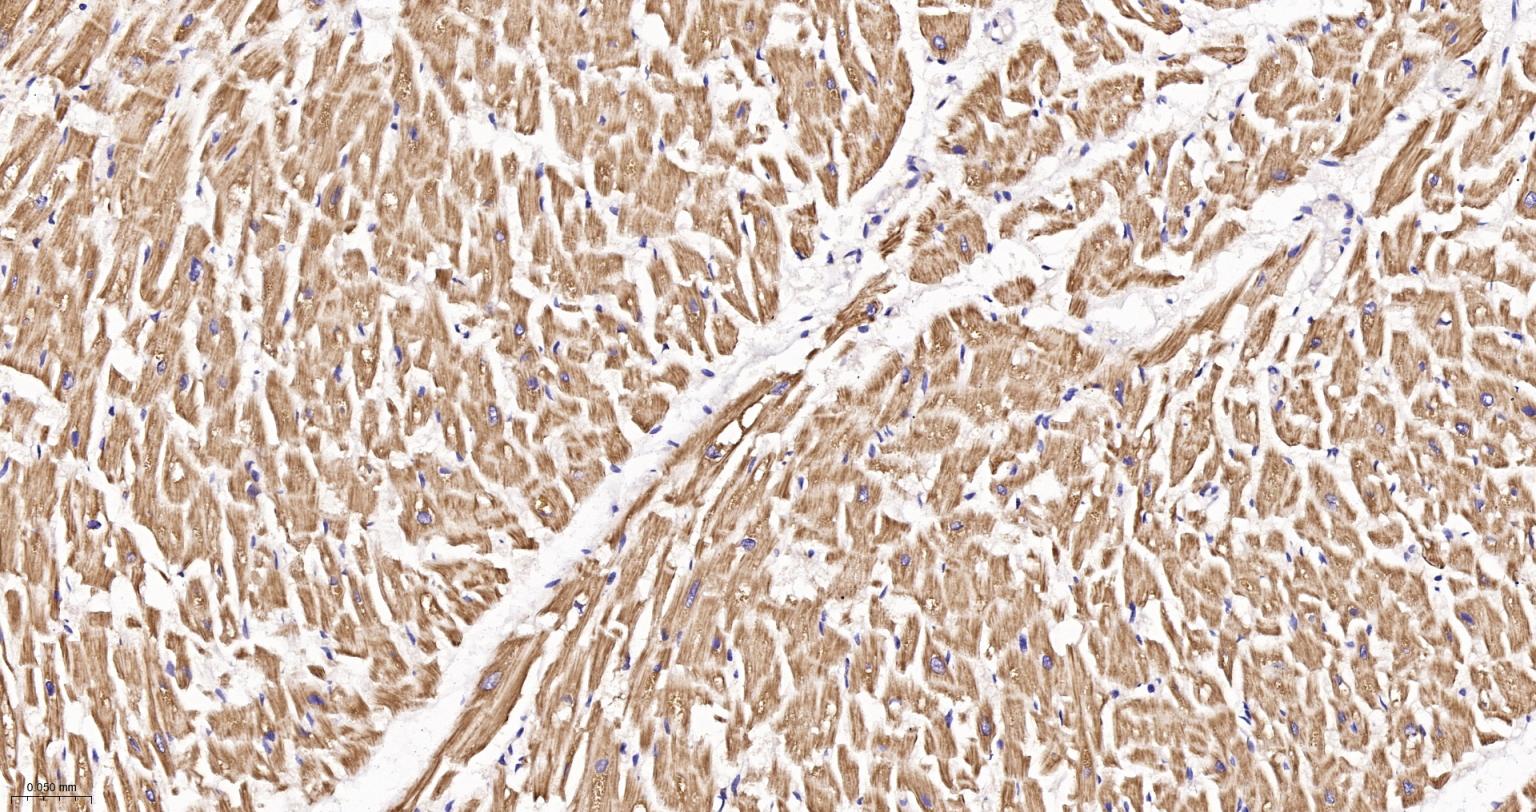

Paraformaldehyde-fixed, paraffin embedded Rat Heart; Antigen retrieval by boiling in sodium citrate buffer (pH6.0) for 15 min; The section was incubated with ATP5MC1 Monoclonal Antibody, Unconjugated (bsm-61256R) at 1:200 overnight at 4°C, followed by conjugation to the bs-0295G-HRP and DAB (C-0010) staining.

Paraformaldehyde-fixed, paraffin embedded Mouse Heart; Antigen retrieval by boiling in sodium citrate buffer (pH6.0) for 15 min; The section was incubated with ATP5MC1 Monoclonal Antibody, Unconjugated (bsm-61256R) at 1:200 overnight at 4°C, followed by conjugation to the bs-0295G-HRP and DAB (C-0010) staining.